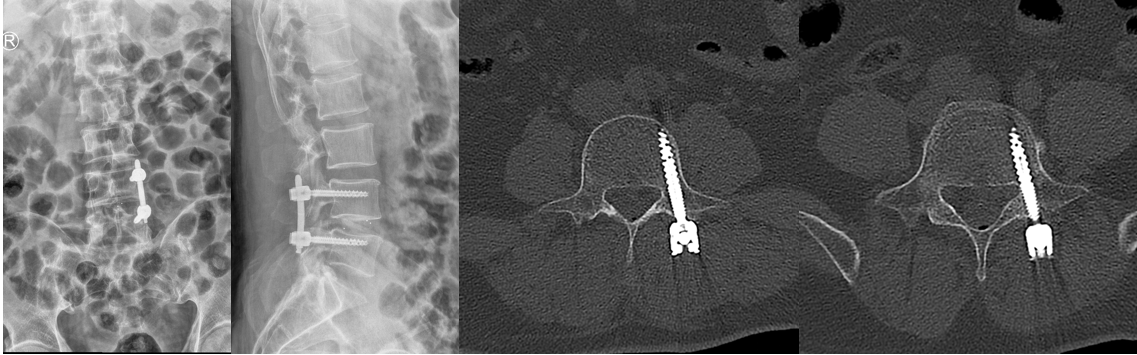

CT示手术机器人规划好的置钉通道位置良好

经过充分和精心的术前准备,姜为民主任医师团队成功为患者施行“内镜下腰椎间盘融合术+经皮椎弓根钉内固定术”,术中借用O臂机和手术机器人,通过先进的影像引导系统,对患者的脊柱进行准确的三维重建和规划。手术医生在计算机屏幕上看到患者的脊柱结构,并根据个体化的解剖特征进行术前计划,为手术提供了更准确的定位和手术路径规划,将误差控制在1mm以内。此次手术过程仅1.5小时,术中出血量不足50ml,伤口为两个1cm切口,符合当前微创及快速康复理念。术后第3天,患者可以下床活动,对术后疗效非常满意。